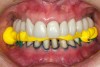

Figure 30  Final restorations.

Figure 30

Figure 31  Technical precision and artistic skill blend into pleasing smile and happy patient.

Figure 31